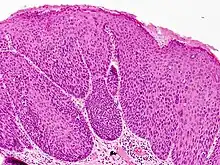

Bowenoid papulosis is a cutaneous condition characterized by the presence of pigmented verrucous papules on the body of the penis.[1]: 730 [2]: 408 They are associated with human papillomavirus, the causative agent of genital warts.[3] The lesions have a typical dysplastic histology and are generally considered benign, although a small percentage will develop malignant characteristics.

It is considered as a pre-malignant condition. Other terms used to describe the condition are: Erythroplasia of Queyrat, Squamous cell carcinoma in situ and Bowen's disease. The term bowenoid papulosis was coined in 1977 by Kopf and Bart and is named after dermatologist John Templeton Bowen.[4][5][6] The term "intraepithelial neoplasia" defines a premalignant intraepithelial change.